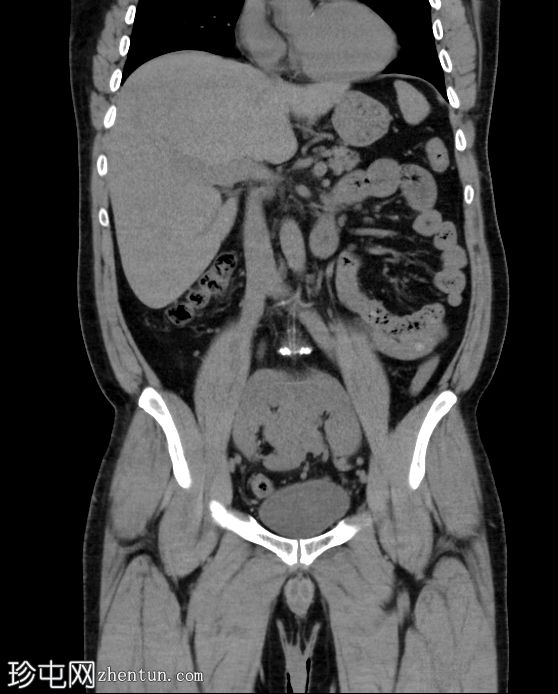

轴位增强扫描(门静脉期)

冠状位增强扫描(门静脉期)

双肾上极和下极融合,形成扁平肾,在轴位、冠状位和三维图像上均可见。

有两条独立的输尿管,左右输尿管分别独立引流至膀胱。

未见结石或反流压力改变。

本病例展示了扁平肾,这是一种解剖变异,其特征是双肾上极和下极完全融合。这与马蹄肾不同,马蹄肾仅下极通过峡部连接。

虽然扁平肾可能是一种偶然发现,但评估是否存在相关并发症(如肾结石和反复

泌尿

道感染)非常重要。